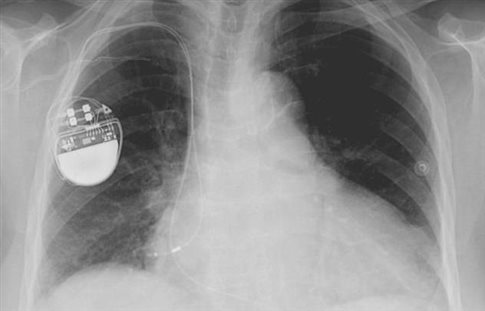

Οι ηλεκτρονικοί βηματοδότες λειτουργούν ουσιαστικά ως τεχνητοί φλεβόκομβοι και αποκαθιστούν τον κανονικό καρδιακό ρυθμό. Σώζουν χιλιάδες ζωές κάθε χρόνο, απαιτούν όμως χειρουργική επέμβαση για την τοποθέτησή τους, χρειάζονται αλλαγή μπαταρίας κάθε λίγα χρόνια και ενέχουν τον κίνδυνο μόλυνσης. Τη λύση θα μπορούσε να δώσει η γονιδιακή θεραπεία που δοκίμασαν σε χοίρους ερευνητές του Ιατρικού Κέντρου «Κέδροι του Σινά» στο Λος Άντζελες. Η μελέτη δημοσιεύεται στην επιθεώρηση Science Translational Medicine.